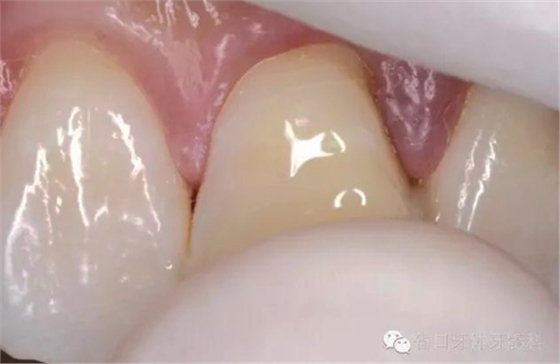

斷冠粘接前試對(duì)接

DUO-LINK樹脂水門汀(BISCO)對(duì)位粘接,(牙齦紅腫,沒有安放橡皮障)

光固化,去除多余樹脂水門汀,近中鄰面洞和舌側(cè)開髓孔樹脂充填,拋光,調(diào)整咬合。